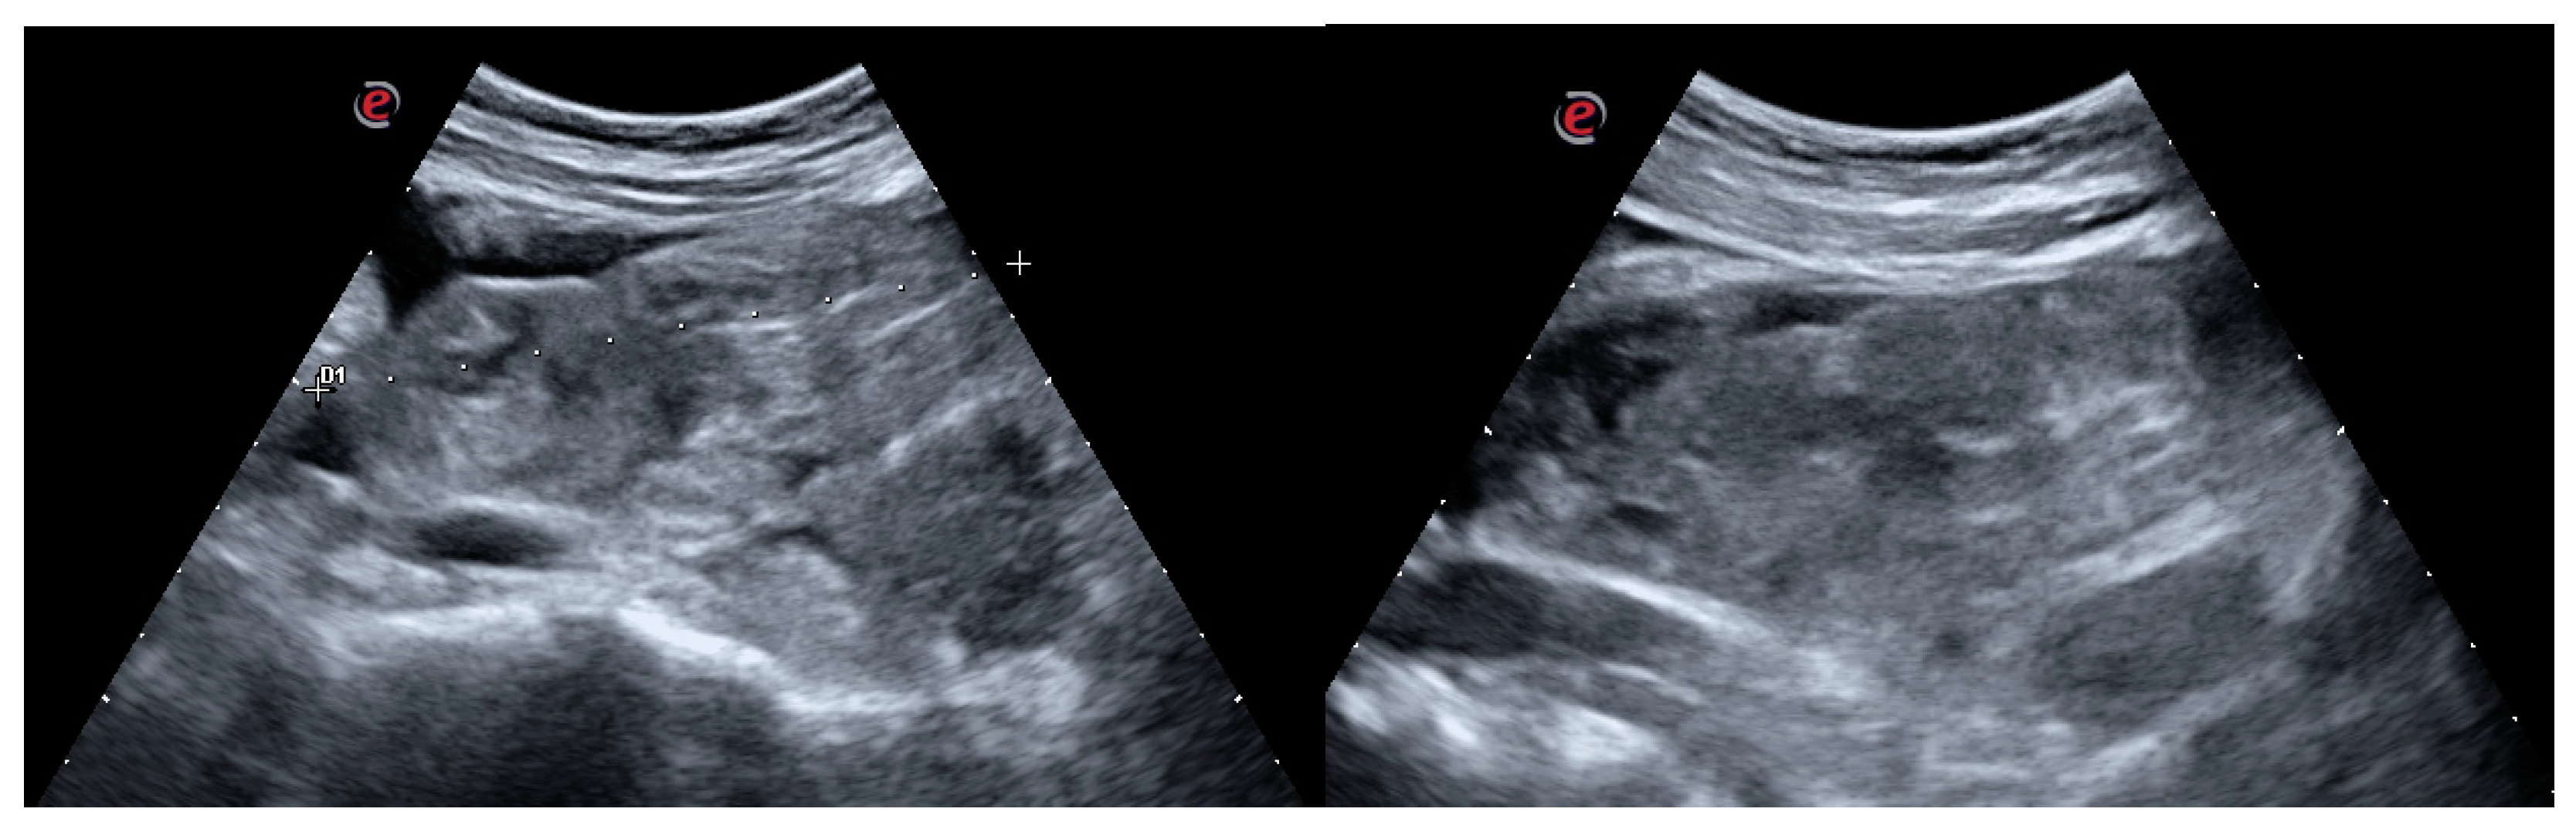

Because of the limited degrees of movement, in order not to damage the appendicovesicostomy, the contemporary US examination was performed till the complete clot disruption (Figure 4a–d).

Figure 4. (a-b-c-d) Intraoperative US evaluation: the intraoperative US examination improved the assessment of the progressive clot disruption till its complete disappearing.